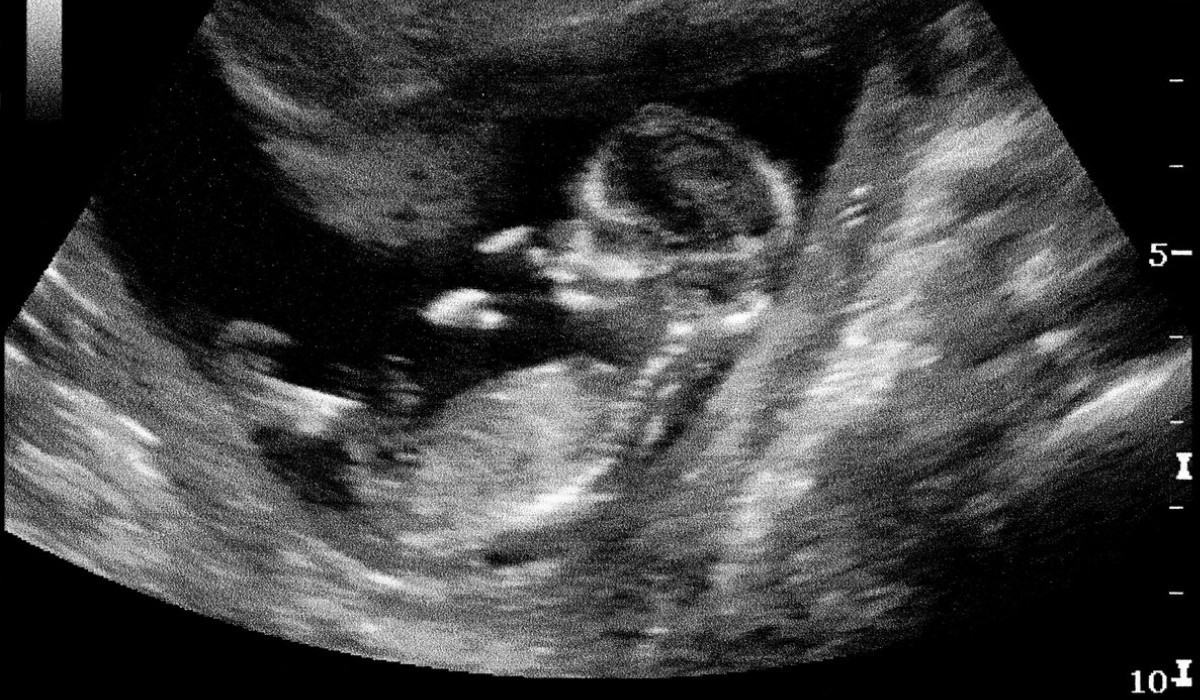

Naşterea este cel mai important moment din viaţa unei femei. Dar odată cu acest moment, apare şi o dilemă importantă: natural sau cezariană? Teoretic, este o alegere personală şi asumată, alături de medic. Practic, în România, de multe ori se dovedeşte a fi o decizie forţată.